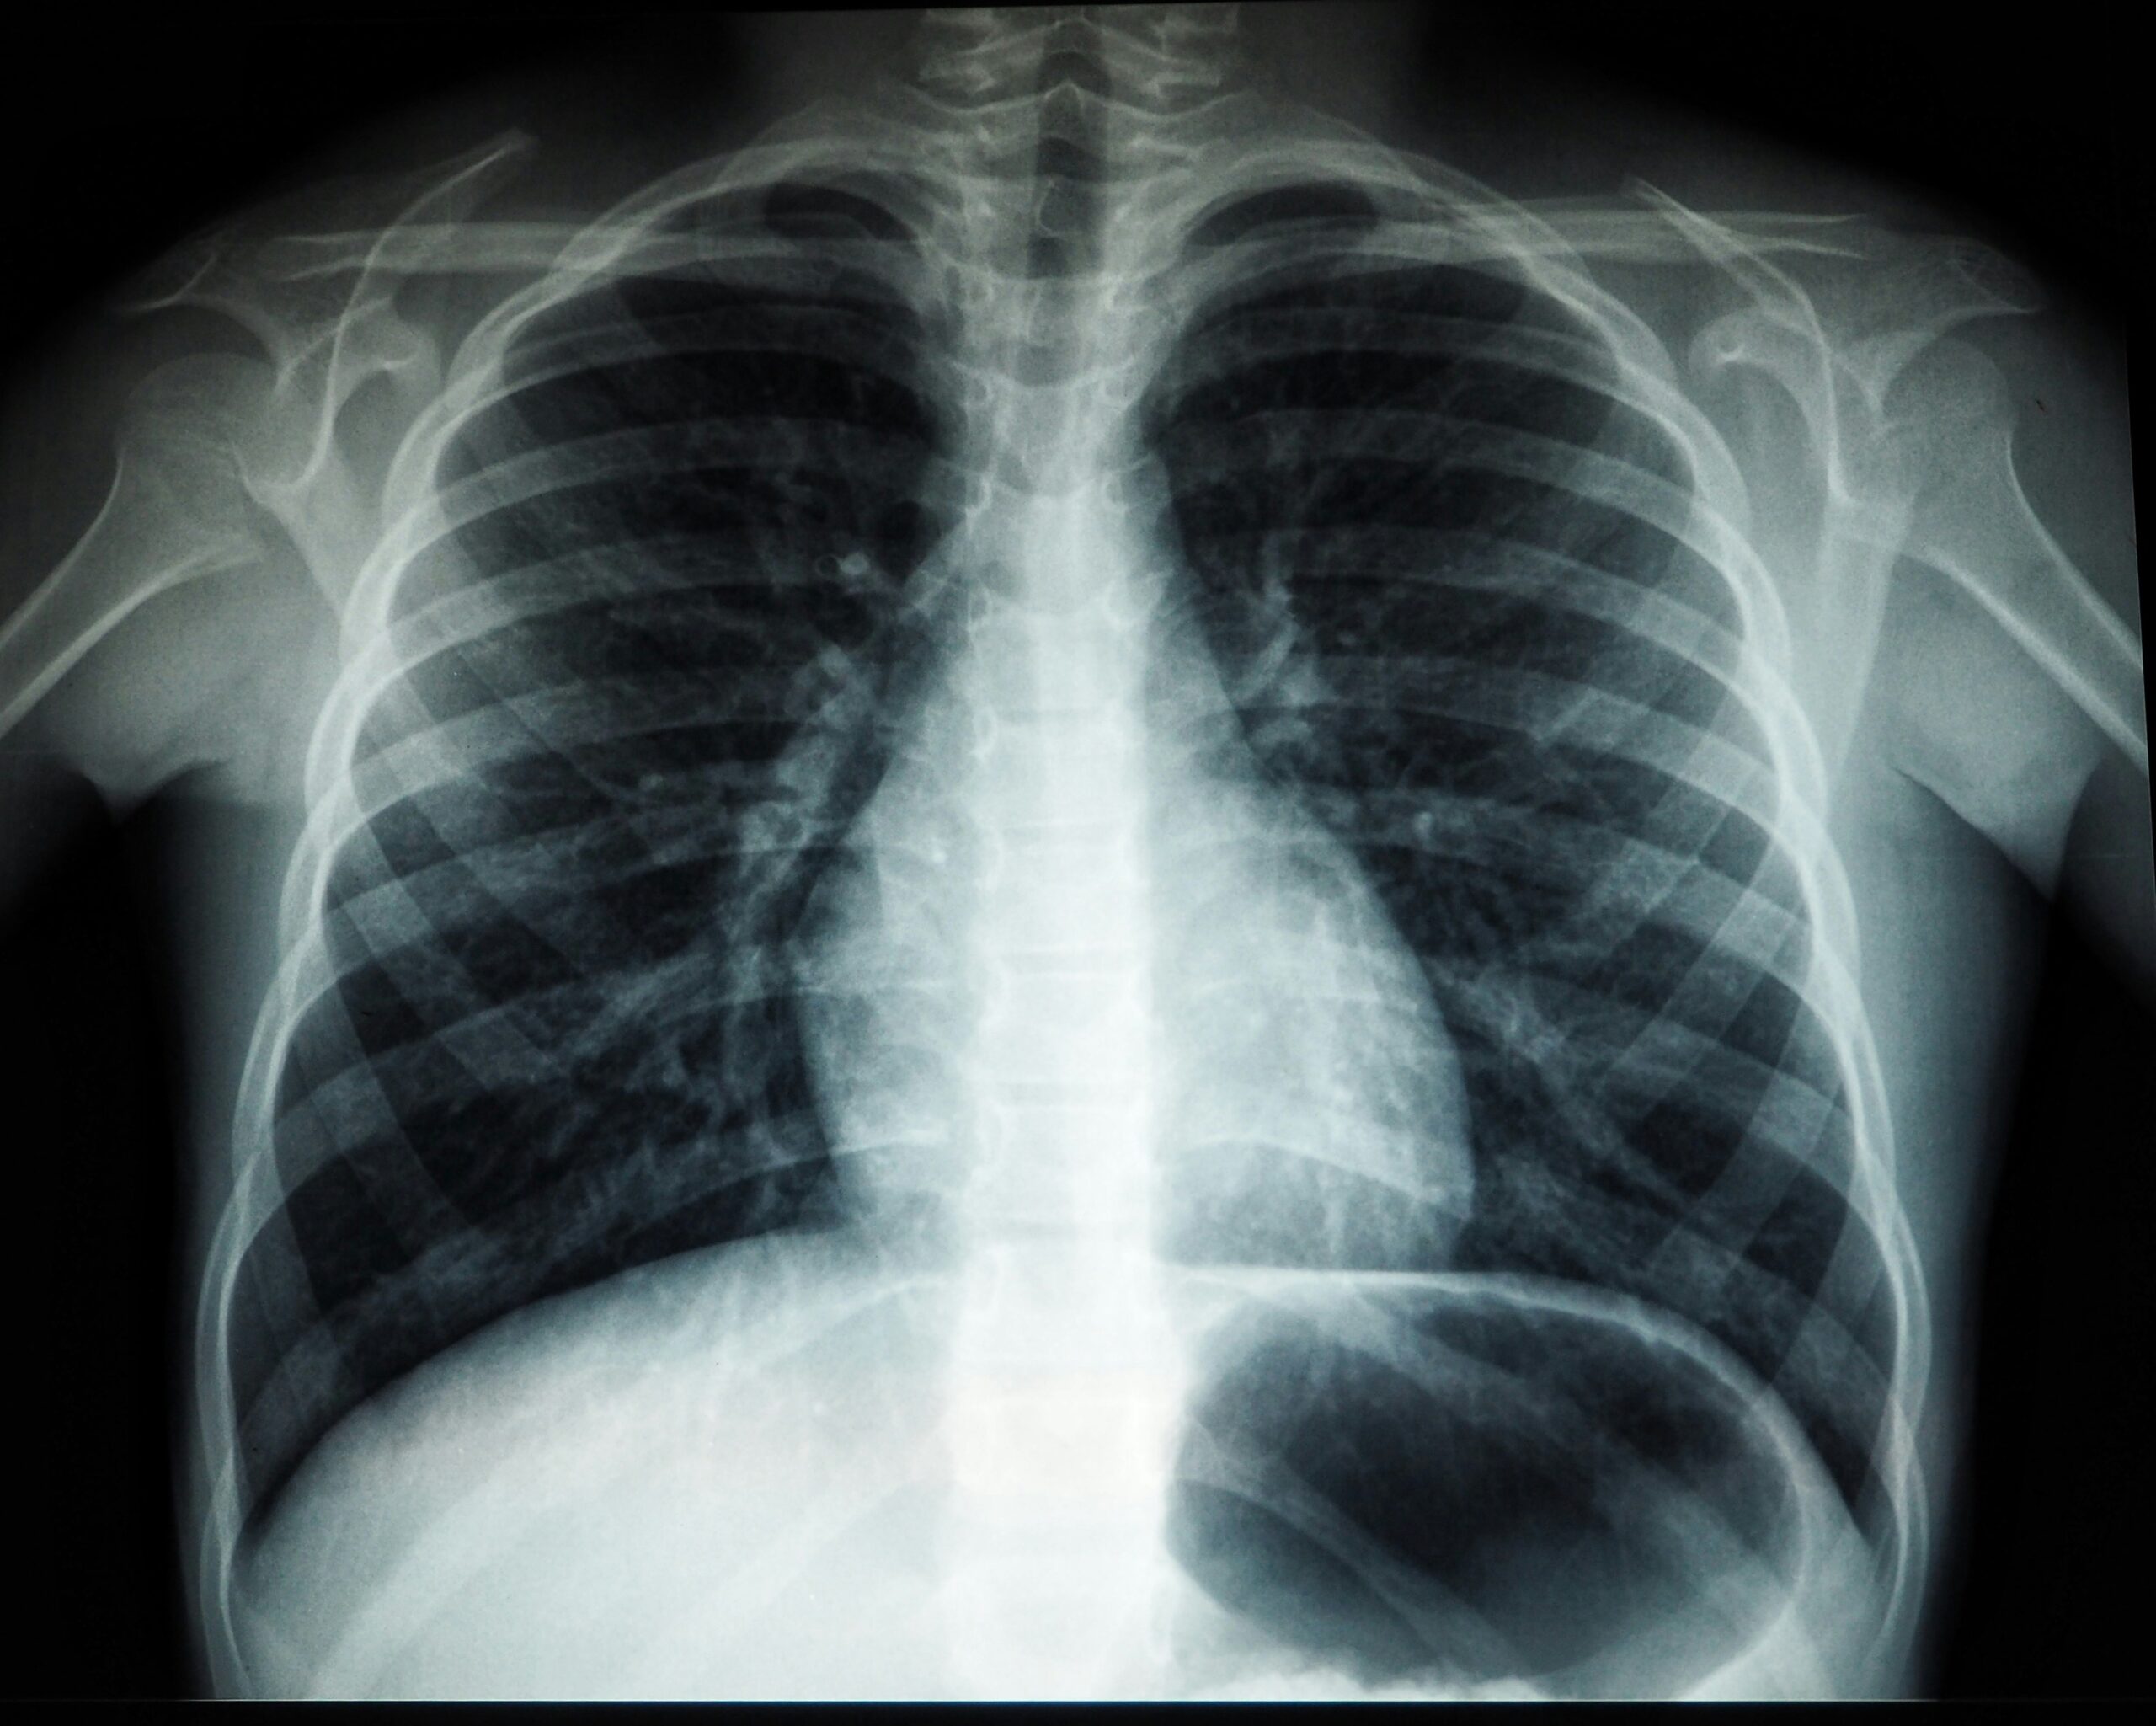

• Diagnosis involves tests such as GeneXpert, sputum microscopy, X-rays, and sometimes biopsies.

• Presumptive TB: Showing symptoms or chest X-ray suggestive of TB

• Other tests: Chest X-ray, ultrasound, biopsies, tuberculin skin test (TST) in children